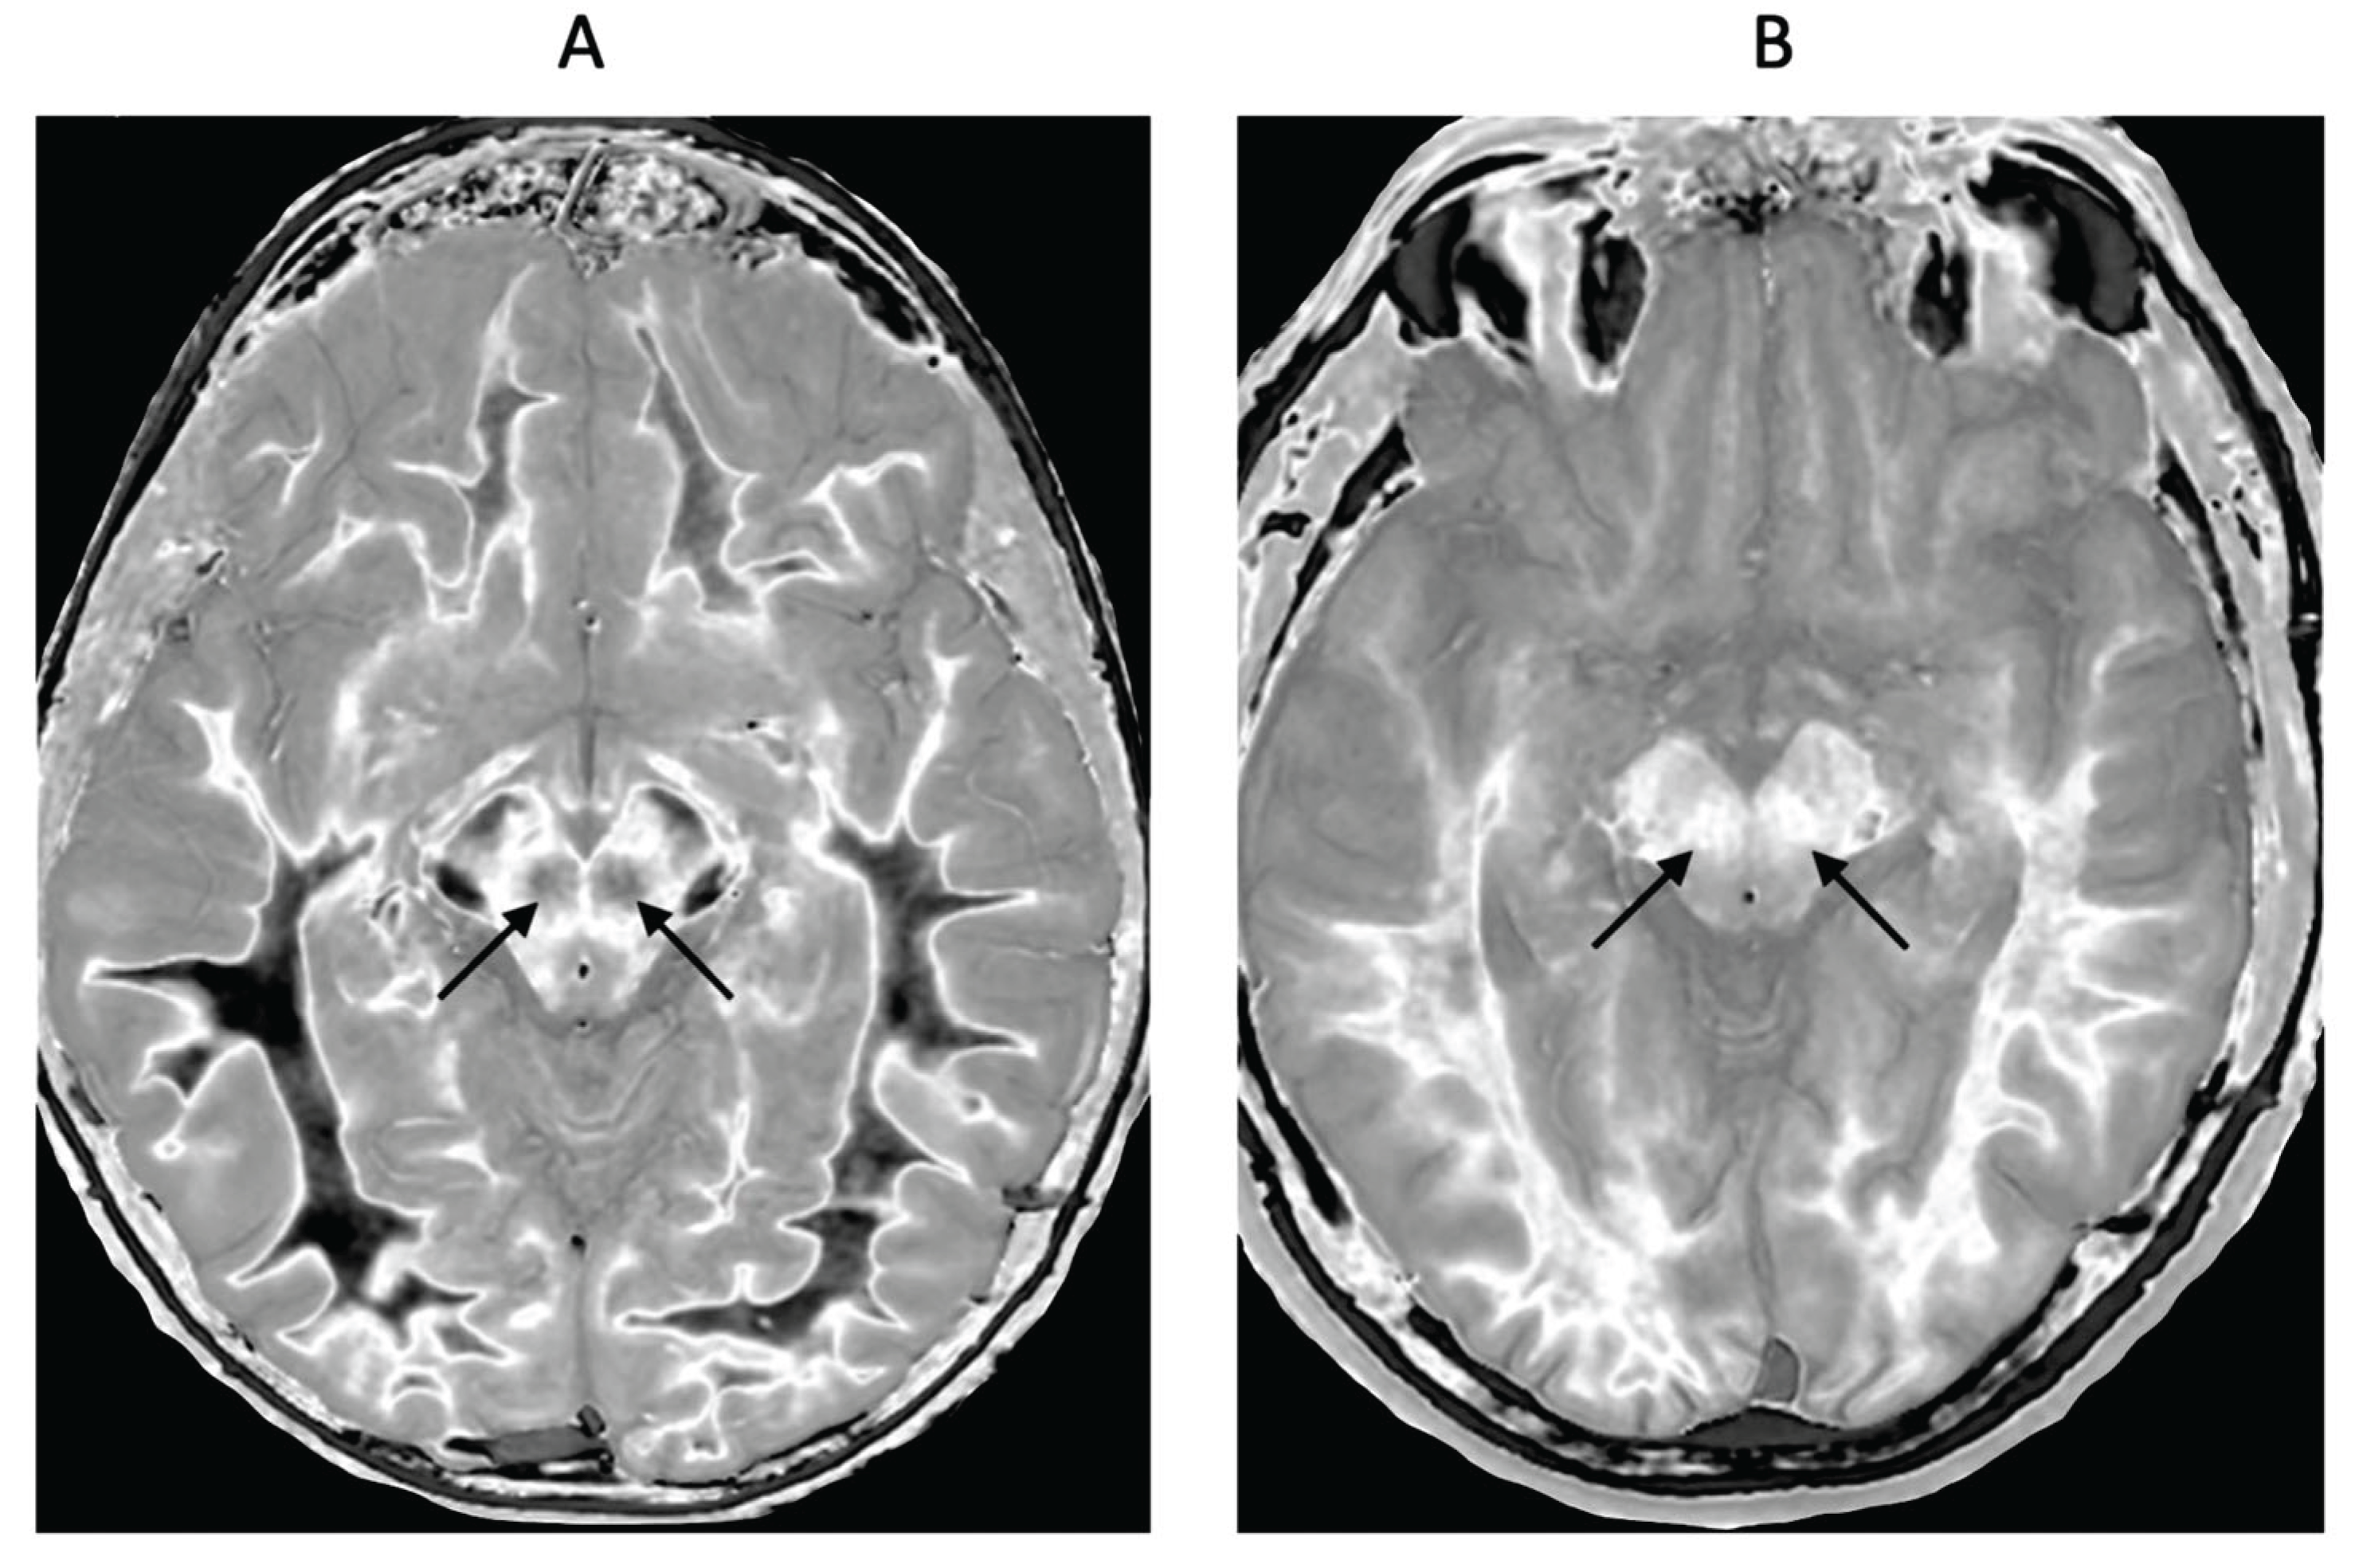

- Parkinson’s Disease